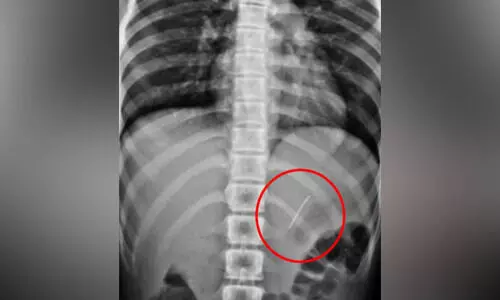

പെരിന്തല്മണ്ണ: ആമാശയത്തിൽ കുടുങ്ങിയ പിൻ സർജറി കൂടാതെ പുറത്തെടുത്തു. തമിഴ്നാട് ഗൂഡല്ലൂര്...